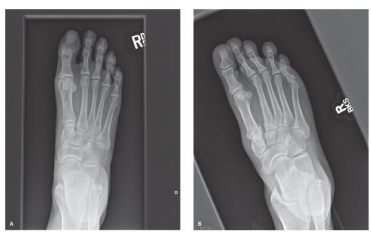

Um paciente de 46 anos compareceu ao setor de

emergência com trauma e dor no pé direito. Após a

realização do exame de imagem, representado abaixo, é

possível chegar à seguinte conclusão: